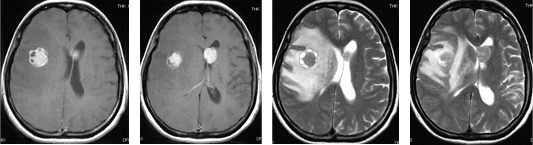

症例 3

乳癌による転移性小脳腫瘍に対して開頭腫瘍摘出術を施行しました。ダンベル状の多発病変でしたが、一期的に摘出しました。術後放射線治療を行いました。

またガンマナイフなど局所放射線治療により脳浮腫が増悪する可能性があると言われる腎臓癌の脳転移では、たとえ腫瘍サイズが小さくても開頭手術を優先した方が良い場合があります。

腎臓癌の脳転移巣は腫瘍サイズが小さい割に脳浮腫が強い場合が多いです。写真で呈示した如く転移性脳腫瘍の肉眼所見は、血管奇形や血管腫と似ており正常脳との境界がわかりやすいため比較的摘出は容易です。また広範囲な脳浮腫も腫瘍を全摘すると消失します。